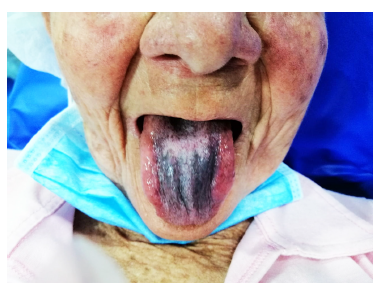

Durante la endoscopia se encuentra lengua de coloración oscura negruzca en su dorso, con aspecto de “pelos”, sin compromiso en los bordes ni en la punta, con zona de despigmentación blanquecina en la zona central posterior (Figuras 1 y 2). En el esófago medio (25 cm), por paredes laterales derecha, izquierda y anterior, hay lesión nodular, infiltrante y friable que produce estenosis franqueable de 12 mm y llega hasta los 30 cm, sin compromiso esofágico distal (Figuras 3 y 4).

Figura 2 Paciente con lengua negra pilosa (LNP), con despigmentación blanquecina en la parte central posterior.

La lengua negra pilosa (LNP) es una condición benigna que consiste en el oscurecimiento y apariencia velluda (“peluda”) del dorso de la lengua, descrita por primera vez por Amatus Lusitanus en 1597 7,8. Su prevalencia es variable, aunque en estudios de salud oral es tan alta como del 11,3%, más común en hombres de la tercera edad, fumadores severos, consumidores de té negro y café 9,10, VIH positivos, edéntulos, con cáncer de próstata o linfoma de células B 6, y en los pacientes en tratamiento con antibióticos 2-4. Clínicamente se observa una placa o membrana negra distribuida en el dorso de la lengua, sin compromiso lateral ni de su punta (Figura 1) y, como en este caso, sin compromiso en la parte central y posterior (Figura 2). El cambio de color más común es negro, pero varía a café, verde o amarillo 11.